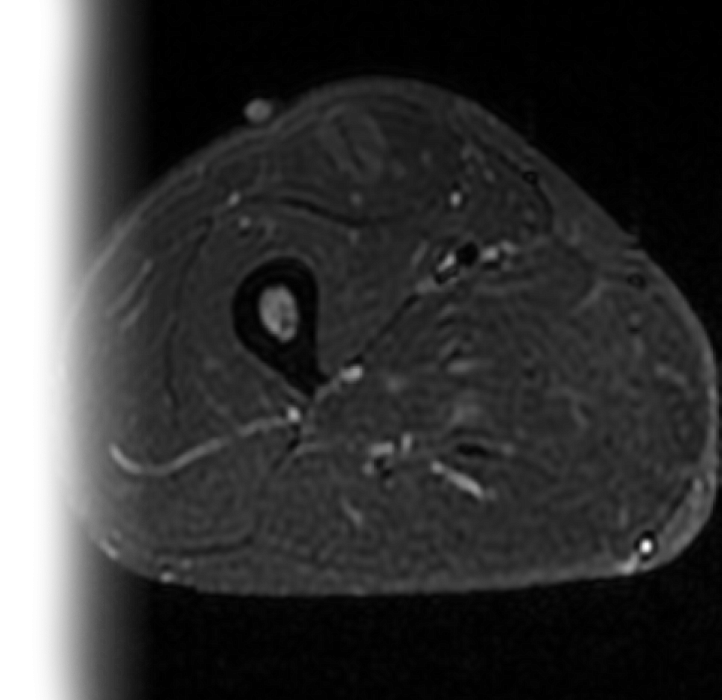

Магнитно-резонансная томография мягких тканей – важный метод исследования, который позволяет оценить состояние мягких тканей одной анатомической области.

Как проводится МРТ мягких тканей?

После этого пациент ложится на стол сканера, который постепенно перемещается в аппарат. Во время сканирования следует лежать неподвижно, чтобы получаемые изображения были четкими и неискаженными.